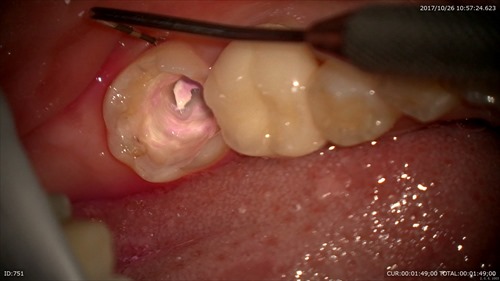

本日はエンド、ペリオ(重症のむし歯で神経が死に歯周病を併発した)患者さまの型とりの日でした。下記のように根の先に膿が出来てしまいそれが歯周ポケットと交通しています。ポケットは9mm。割れてはいないようでした。

CTでこのように精密に診断することにより的確な治療方法がお話でき納得されていました。

根管治療→歯周病治療→再検査→かぶせ物の計画です。